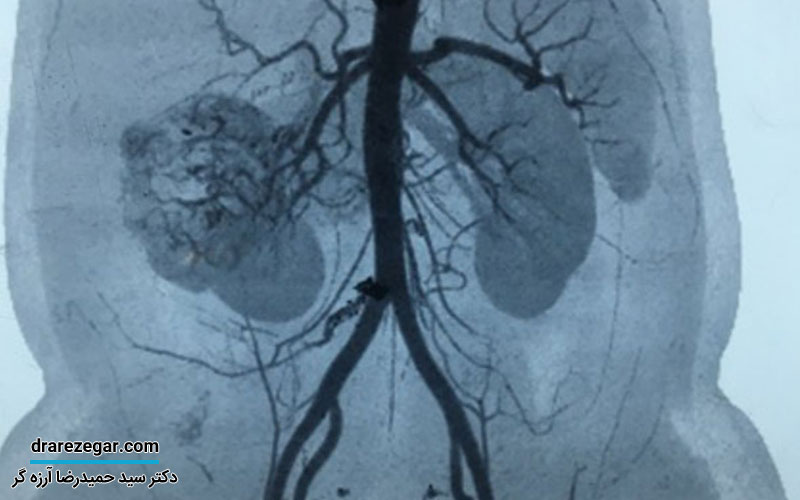

سیتی آنژیو : دقیقترین روش برای مشاهده لخته، مسیر جریان خون و وضعیت وریدهای کلیوی.

امآرآی آنژیوگرافی: روش بدون اشعه با دقت بالا، مناسب برای بیمارانی که امکان انجام CT ندارند.